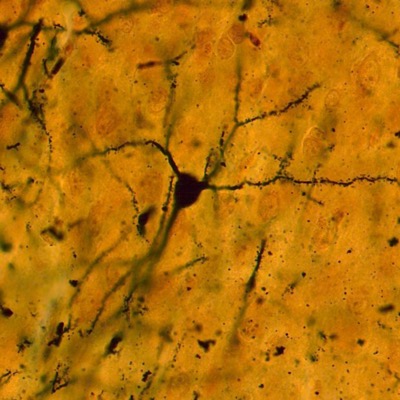

La neurona o célula nerviosa es la unidad funcional del sistema nervioso. Está compuesta por el soma que contiene el núcleo y varias evaginaciones de longitud variable. Las células gliales son células no conductoras. El SNC contiene cuatro tipos de células gliales: los oligodendrocitos, los astrocitos, la microglía y los ependimocitos. Estas células se denominan glía central. En el sistema nervioso periférico (SNP), las células de sostén se denominan glía periférica e incluyen las células de Schwann, las células satélites y otras células asociadas con estructuras específicas.

Neuronas